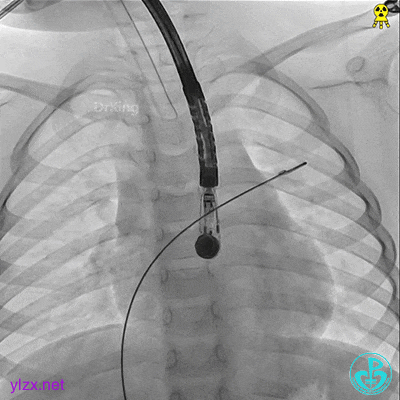

左盘展开

左盘展开,牵拉成型线,使左盘面成型。

右盘展开

右盘展开,牵拉成型线使得封堵器双盘扣合住间隔。